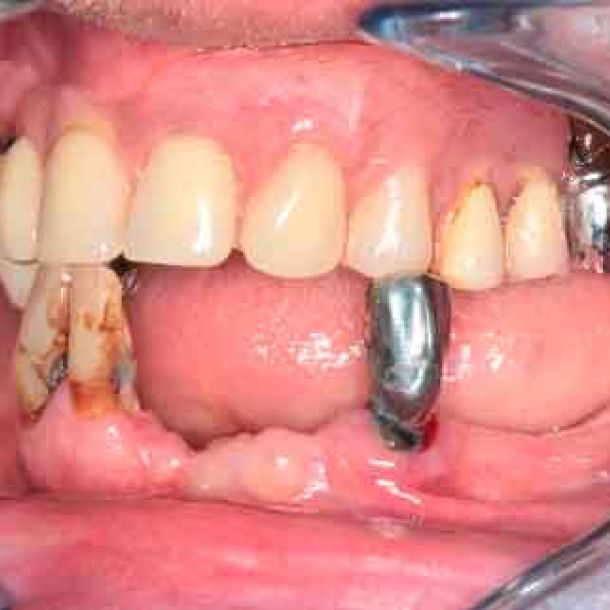

Situation

66 years old patient. Wishes to regain functional comfort and improve aesthetics.

Complaints :

- Lack of stability of his removable prosthetics

- Difficulties in eating

- Sagging of the upper lip

The periodontal structures of the remaining teeth are no longer sufficient. An edentulism is considered. The treatment plan is directed towards a removable maxillary complete prosthesis and an implant-supported mandibular complete prosthesis.